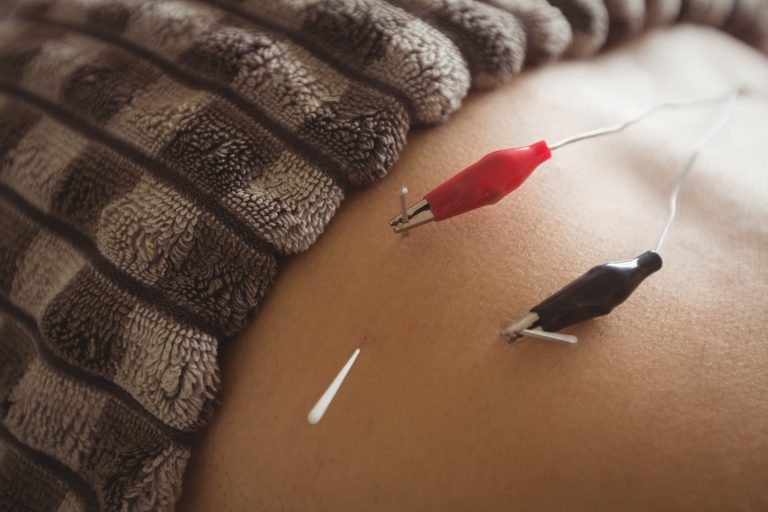

Akupunktur merupakan rawatan berasaskan Perubatan Tradisional Cina (TCM) yang telah diamalkan selama ribuan tahun. Dalam konteks cara merawat minor stroke, akupunktur berfungsi melalui rangsangan titik-titik tertentu pada tubuh bagi mengaktifkan sistem penyembuhan semula jadi.

Kajian menunjukkan bahawa akupunktur mampu meningkatkan aliran darah otak, merangsang saraf, serta membantu pemulihan motor dan deria dengan lebih cepat.

Pesakit minor stroke sering mengalami kebas, lemah otot, atau koordinasi yang terganggu. Akupunktur merangsang sistem saraf pusat dan periferi, membantu mempercepatkan pemulihan fungsi yang terjejas. Ini menjadikannya antara cara merawat minor stroke yang efektif tanpa kesan sampingan serius.

Berbanding penggunaan ubat jangka panjang, akupunktur adalah rawatan semula jadi yang selamat apabila dilakukan oleh pengamal bertauliah. Ia boleh digabungkan dengan rawatan hospital sebagai pelengkap dalam cara merawat minor stroke tanpa risiko interaksi ubat.